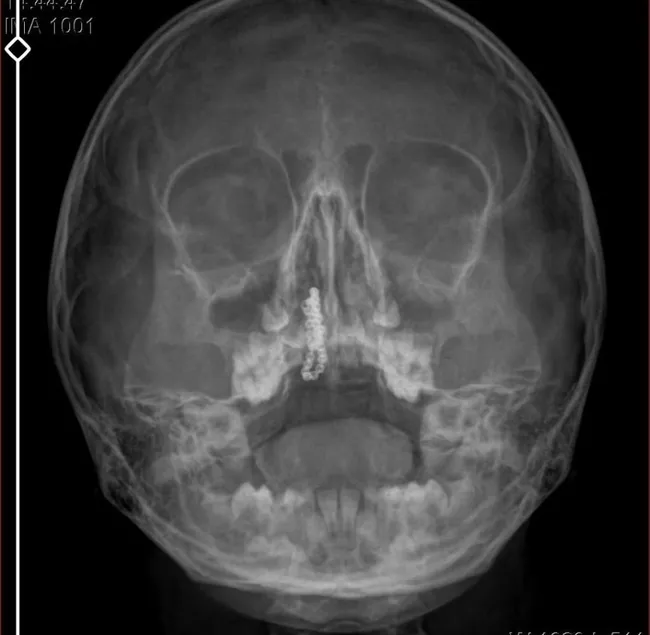

Devlet hastanesindeki doktorun incelemesi ve kapsamlı röntgen çekilmesi sonrası Polen'in burnunda metal cisim olduğu fark edildi. 2 yıldır burunda kaldığı değerlendirilip, küçük top şeklinde tırnak makası zinciri olduğu belirlenen cisim, başarılı ameliyatla çıkarıldı. Bir süre tedavisi sürdürülen Polen, sağlığına kavuşunca taburcu edildi. Özel hastane yetkilileri, konuyla ilgili açıklama yapmazken; aile suç duyurusunda bulunacaklarını söyledi.

Burunda metal zinciri fark ettiler. Böyle bir ihmalkarlık olabilir mi? Özel hastaneye gidiyoruz, paramızla rezil oluyoruz. Zincir, 2 yıldır burnunda ve devletimizin hastanesinde iyi bir doktorumuz zinciri ortaya çıkarıyor, kızım ölümden dönüyor. Ben sonuna kadar bu işin peşini bırakmayacağım. Sonuna kadar hukuk mücadelesi vereceğim. Bu da diğer hastalarımıza ibret olsun. İşte, bakın koca bir zincir. 'Bulguya rastlanılmadı' deniliyor" dedi.

Kızının ameliyat sonrası durumunun iyi olduğunu söyleyen Tekin, "İnanır mısınız bize 'Evde soba mı yanıyor? Acaba kömür isten dolayı mıdır bu?' dendi. Böyle bir şey olabilir mi? Ameliyattan çıkan parmağım kadar zincir. Devlet hastanesindeki doktor da 'Bu nasıl gözden kaçılabilir? Böyle bir pozisyon nasıl görülmeyebilir?' yorumunda bulundu. Allah'a şükür olsun atlattık. Şu anda durumu, vaziyeti iyidir. Ben şuna inanıyorum doktor da bir şans işidir. Bakın paramızla özele gideriz ya hani bizde, daha iyi ilgilenirler. Oysa devlet hastanesindeki doktorumuz olayı meydana çıkardı" diye konuştu.